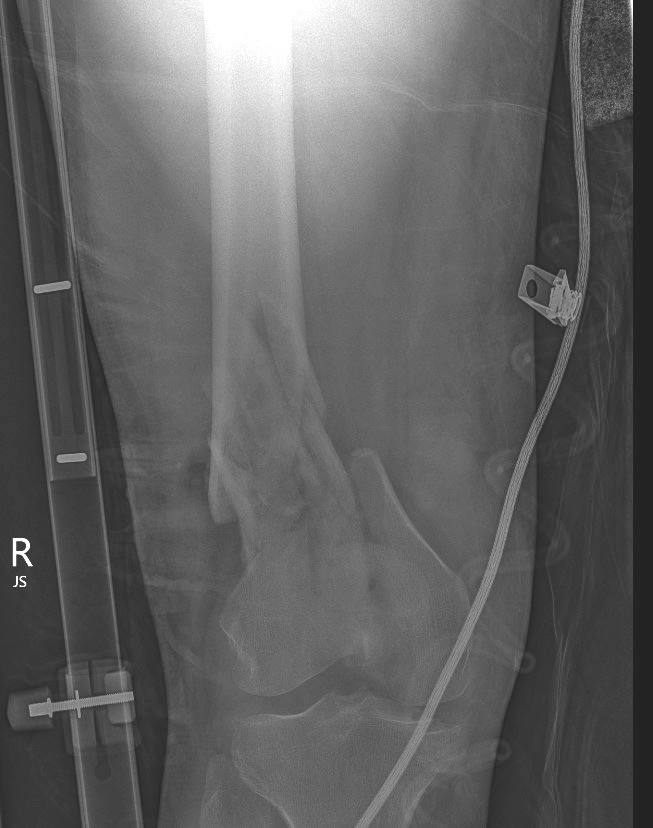

AO Type A: Supracondylar / Extra-condylar

Xray